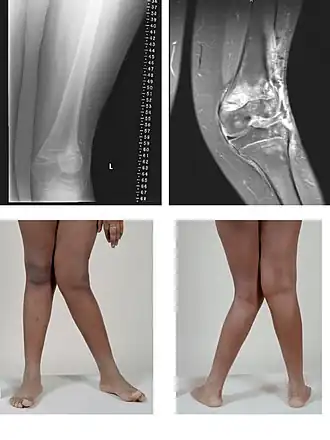

Genu valgum

El eje formado por el fémur y la pierna es más abierto de lo normal, adoptando el miembro inferior un aspecto en X con las rodillas muy juntas y los talones separados. Puede estar presente desde la infancia o aparecer en la vida adulta, muy frecuentemente causado por sobrepeso u obesidad.

Genu varum

En esta deformidad los miembros inferiores tienen una convexidad externa y los cóndilos femorales internos están separados por una distancia superior a los 6 cm. Es por lo tanto una desviación inversa a la que se produce en el genu valgum. Se describe a veces como miembros inferiores en paréntesis, pues los pies están muy próximos y las rodillas separadas en situación de bipedestación (de pie).

Genu recurvatum

El genu recurvatum consiste en una hiperextensión de la articulación de la rodilla superior a los 10 grados. Puede ser de origen congénito, secundario a una parálisis muscular secuela de una poliomielitis o consecuencia de un raquitismo o una rotura de los ligamentos cruzados. Produce inestabilidad durante la marcha y tendencia a la artrosis precoz. Se trata mediante ejercicios de fisioterapia, medidas de rehabilitación, correcciones ortopédicas y tratamiento quirúrgico en los casos graves.[39]

Genu flexum

El Genu flexum es una deformidad de la rodilla en la cual la articulación no puede realizar una extensión completa y por lo tanto se encuentra de forma permanente en una posición de flexión. Es por lo tanto la deformidad inversa al genu recurvatum. Puede ser de origen congénito o adquirido en la vida adulta como consecuencia de artrosis, parálisis muscular o una in-movilización prolongada. Se trata mediante ejercicios de rehabilitación, fisioterapia y cirugía en los casos más graves.